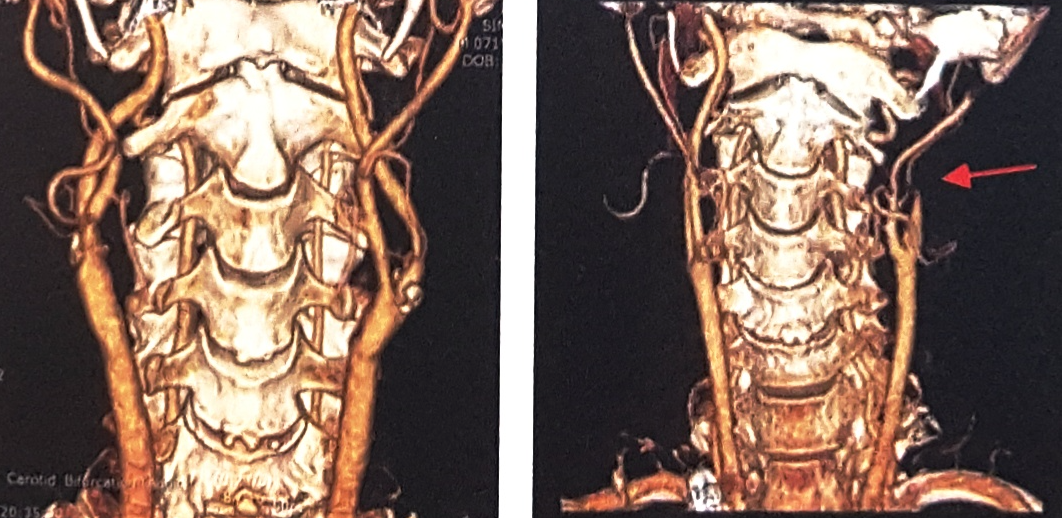

CT(Computed Tomography, 전산화단층촬영)검사는 신체의 일정 원하는 부위에서 단면을 깨끗한 2차원 영상으로 볼 수 있는 검사입니다. 촬영이 끝난 후 이러한 2차 단면영상을 컴퓨터를 이용하여 삼차원(3D)영상으로 재구성하면 동맥이 특별히 잘 보일 수 있도록 입체적인 영상도 얻을 수 있습니다.

대동맥부터 다리 전체의 동맥

다리의 무릎아래 동맥